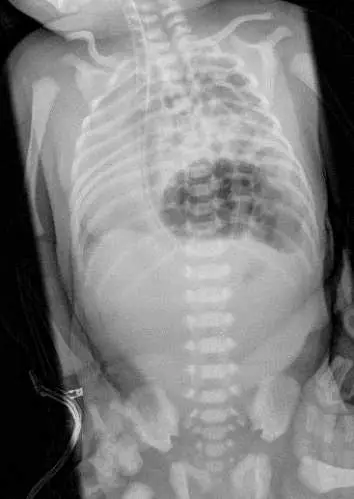

新⽣兒出⽣後即有呼吸窘迫、唇⾊發紫、胸部較腹部來得⾼突的現象。⾝體診察發現最⼤⼼⾳在右側。胸腹部X光片如附圖,最有可能的診斷為何?

X 光片為新生兒胸腹部正面(AP)投影,影像可見以下關鍵發現:

- 左側胸腔充滿氣泡狀陰影:左側胸腔內可見多個大小不一的氣泡狀(bubbly)透亮影,為腸道(bowel loops)疝入胸腔後充氣所形成的特徵性表現,而非正常的肺葉充氣外觀。

- 縱膈腔向右偏移:心臟及縱膈腔結構明顯被推向右側,與題幹描述「最大心音在右側」相符——此為左側胸腔內疝入臟器造成的佔位效應(mass effect)所致。

- 右肺受壓:右側肺野空間相對縮小,肺組織受壓。

- 腹部相對空虛:下腹部腸道氣體影明顯減少,因腸道已疝入胸腔。

- 左側橫膈輪廓消失:無法辨識正常左側橫膈線,為橫膈缺損的間接證據。

上述表現組合——左胸充滿腸道氣泡影 + 縱膈右偏(右位心音)+ 腹部空虛——是**左側先天性橫膈膜疝氣(left-sided CDH,Bochdalek hernia)**的典型 X 光影像診斷依據。